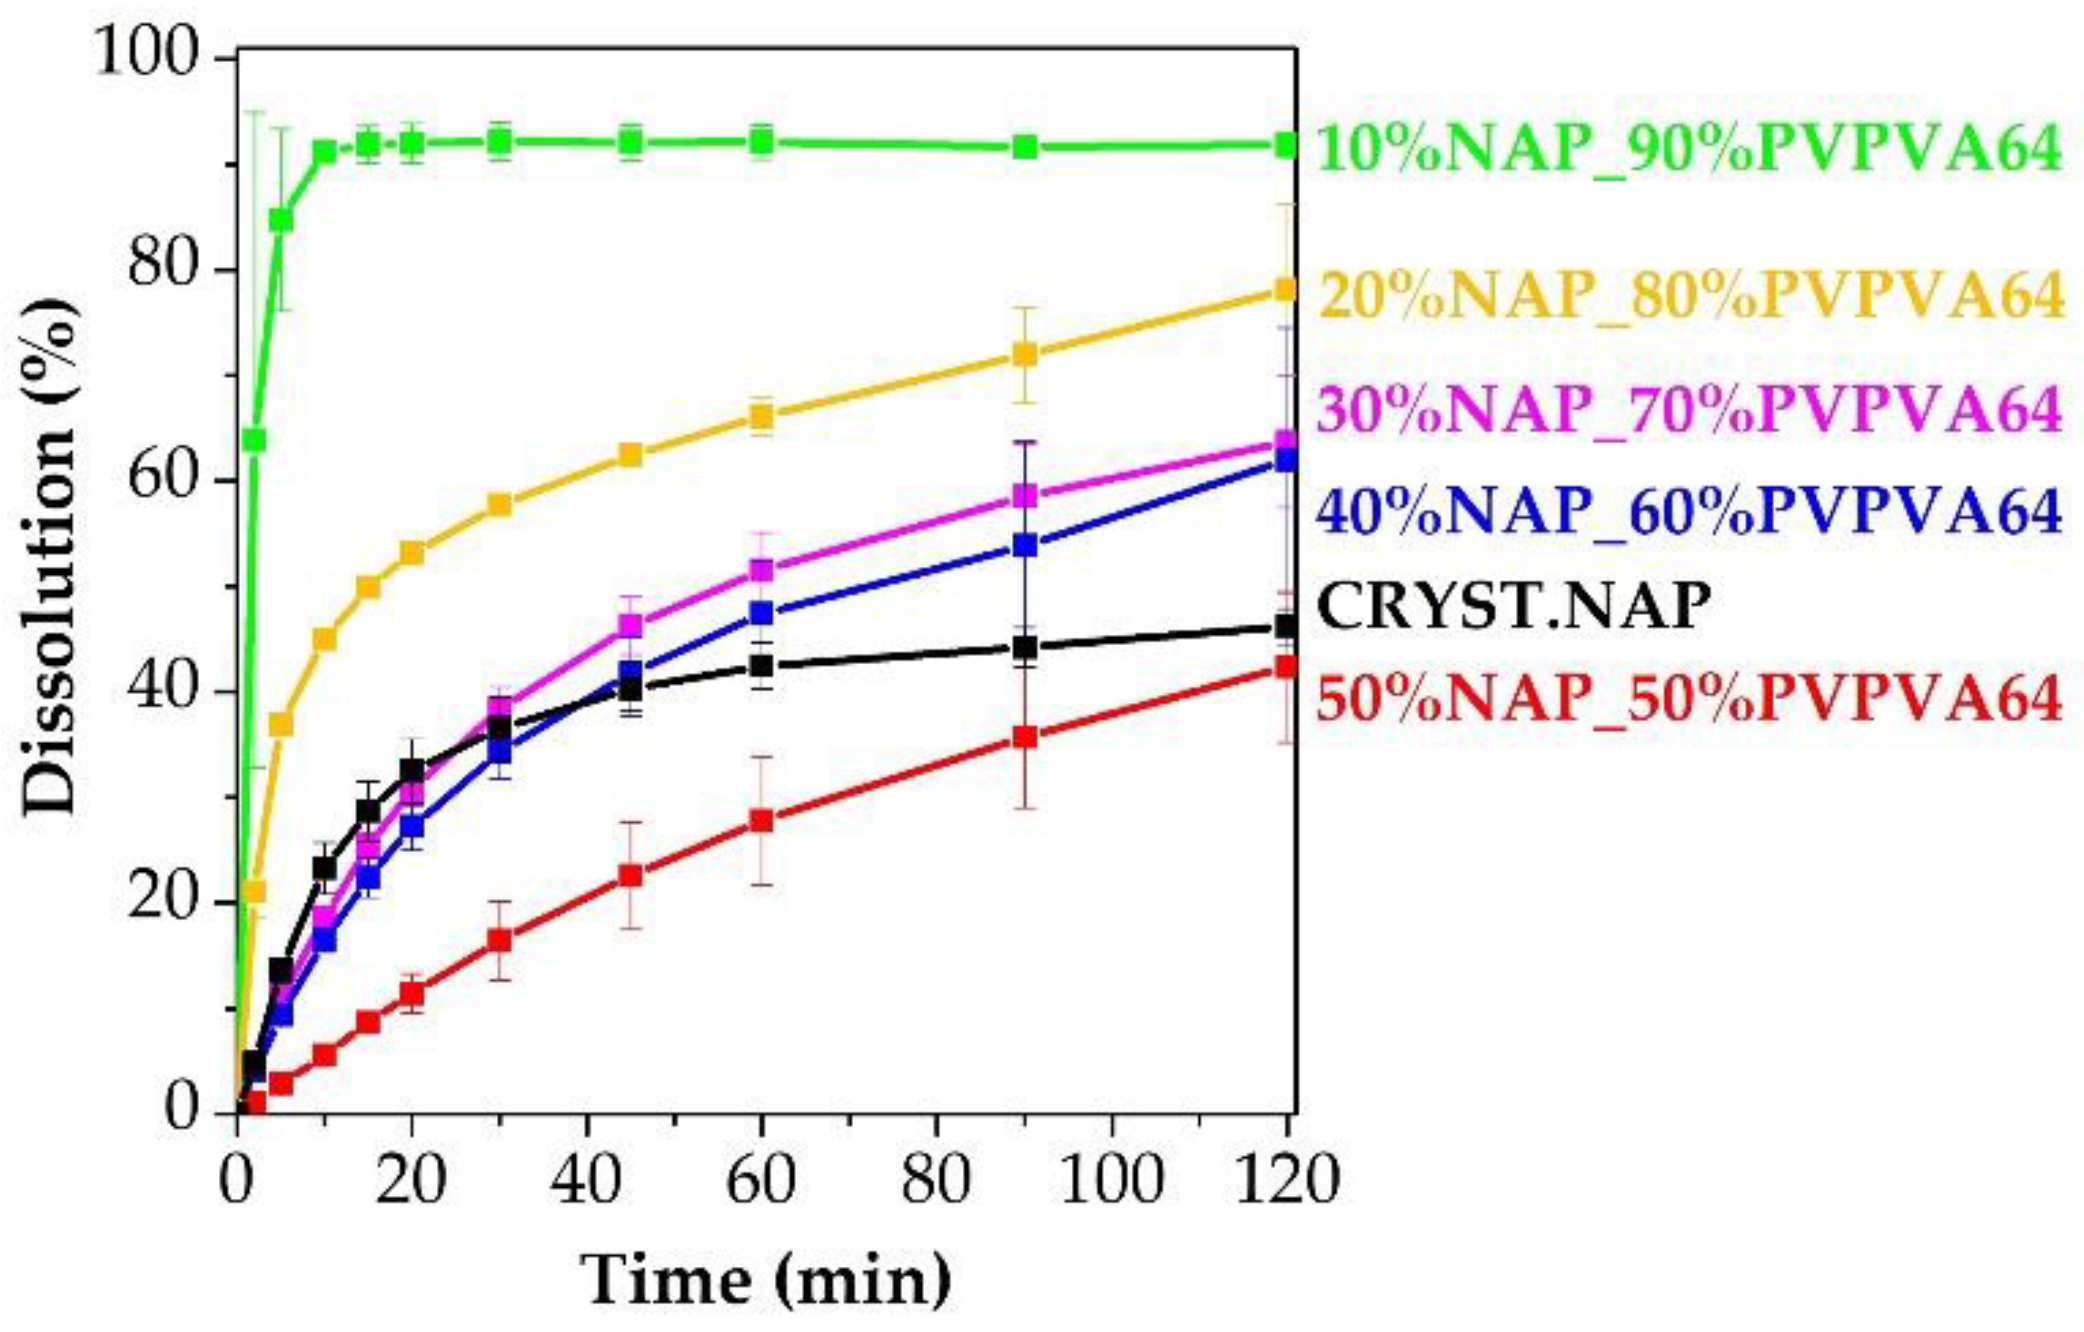

2.11. In Vitro Dissolution Testing

3. Results and Discussion

3.3. Effect of the Stress Stability Tests

3.4. Correlations between the Measured Tg Values and the Stability